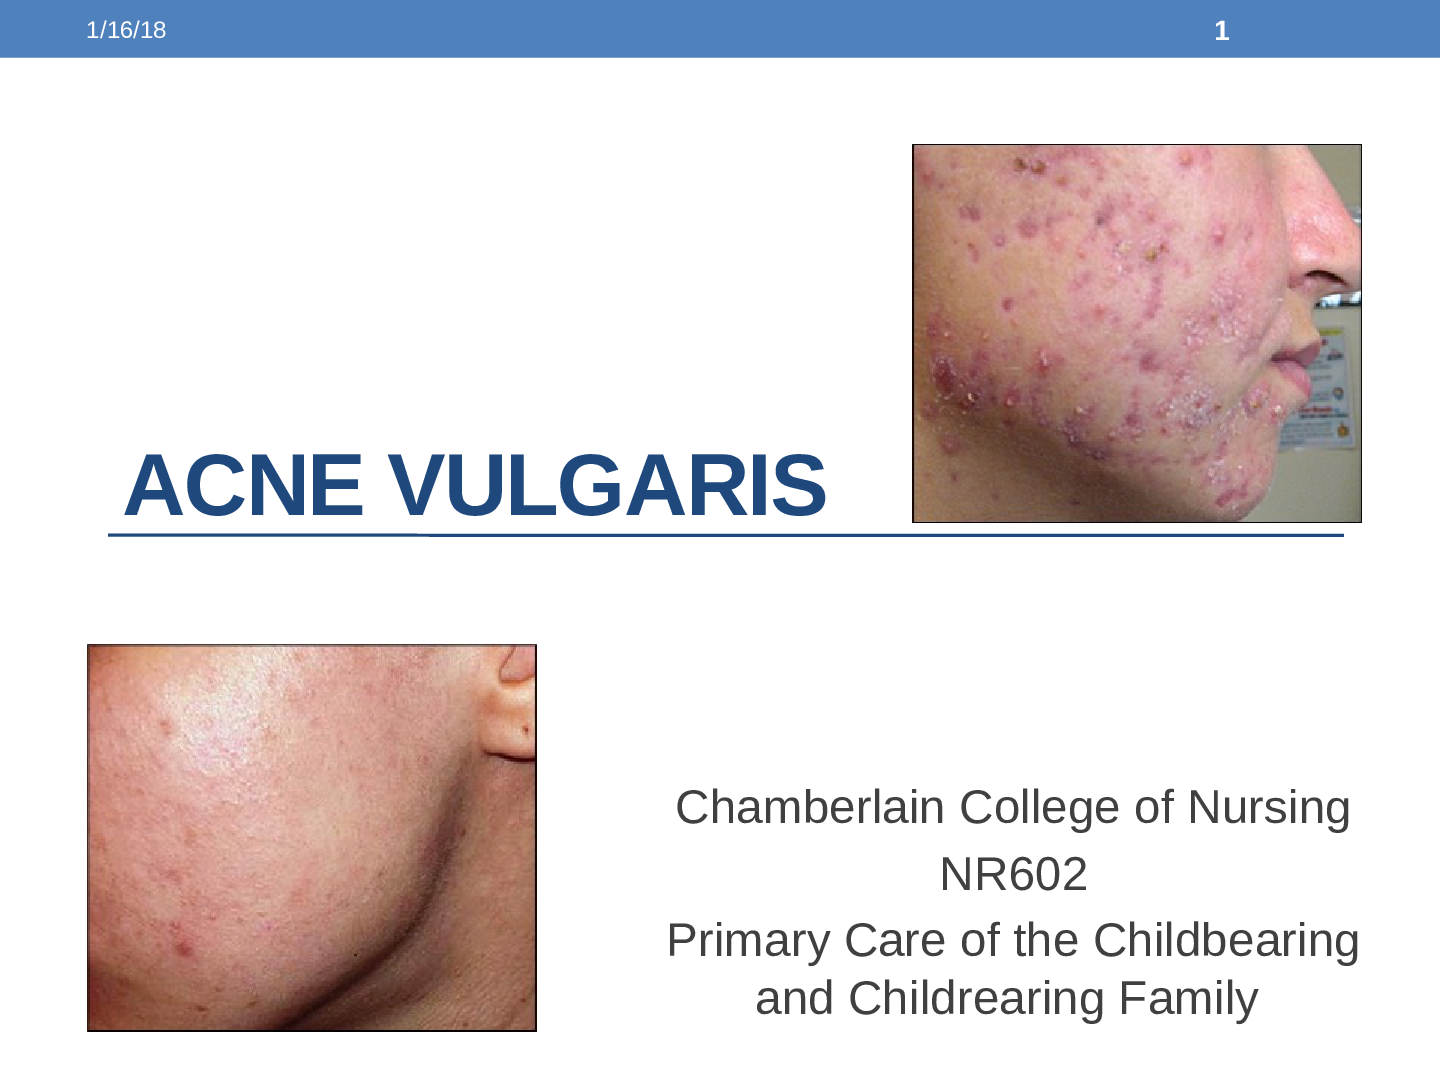

*NURSING> Summary > NR 602 Week 2 Pediatric Grand Rounds Discussion: ACNE Vulgaris (All)

NR 602 Week 2 Pediatric Grand Rounds Discussion: ACNE Vulgaris

NR 602 Week 2 Pediatric Grand Rounds Discussion: ACNE Vulgaris Purpose The purpose of this assignment is to enhance the student’s clinical reasoning, confidence and learning of various pediatric a...

*NURSING> Study Notes > NR 602 Week 2 Pediatric Grand Rounds Presentation and Discussion; ACNE Vulgaris (All)

NR 602 Week 2 Pediatric Grand Rounds Presentation and Discussion; ACNE Vulgaris

NR 602 Week 2 Pediatric Grand Rounds Presentation and Discussion; ACNE Vulgaris Purpose The purpose of this assignment is to enhance the student’s clinical reasoning, confidence and learning of va...